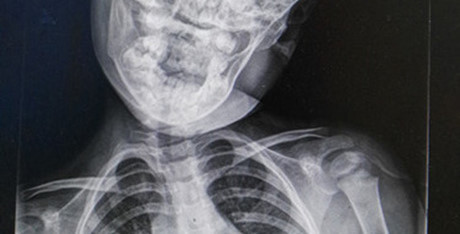

Hình ảnh những đứa trẻ dán mắt vào điện thoại hoặc máy tính bảng không còn xa lạ. Đơn giản là cha mẹ quá bận nên vứt cho con những thứ đó để con ngồi yên. Nhưng tác hại khôn lường. Ngay cả bác sĩ cũng phải sửng sốt trước một bệnh nhân mới 3 tuổi đã bị lệch cổ, thoái hóa đốt sống cổ. Nguyên nhân là do bé được cha mẹ cho chơi điện thoại, Ipad đến phát nghiện.

"Ôm" điện thoại và Ipad, bé 3 tuổi bị lệch cổ, thoái hóa đốt sống

Sau khoảng 1 năm đều đặn sử dụng điện thoại và máy tính bảng, đã phải nhập viện khẩn cấp và trở thành bệnh nhân "nhí" tại khoa Phục hồi chức năng để điều trị bệnh lệch cổ, thoái hóa đốt sống cổ .

Trước đó, vào tối ngày 11/6/2016, bé gái Phương Phương (3 tuổi) tự nhiên bị sốt cao 38,5 ℃. Sang ngày thứ hai thì bố mẹ thấy em có hiện tượng bị vẹo cổ sang bên trái và cứ thế giữ yên không quay được.

Sau khi bác sĩ nhi khoa thăm khám và chẩn đoán là viêm amiđan mủ cấp tính, do cổ của bé có hiện tượng bị hạn chế vận động .

Theo bác sĩ Hồ Tiểu Quân, giám đốc bệnh viện Phổ Nhân, người trực tiếp xem xét bệnh tình của Phương Phương cho biết, bé còn rơi vào hiện tượng căng cơ bắp vùng cổ, xuất hiện đau rõ ràng.

Đây là hiện tượng thoái hóa đốt sống cổ, tổn thương nặng vùng cơ trên phần cổ, cần phải lập tức điều trị phục hồi chức năng, trị liệu nhanh để hồi phục công năng hoạt động của cổ.

Mới chỉ 3 tuổi mà đã bị thoái hóa đốt sống cổ như vậy thì quả thực cần phải báo động đặc biệt đối với các bậc phụ huynh.